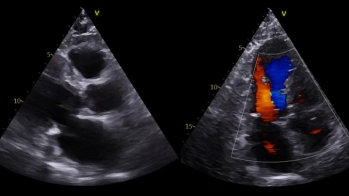

Vidéo 1

Vidéo 2

Vidéo 3

Vidéo 4